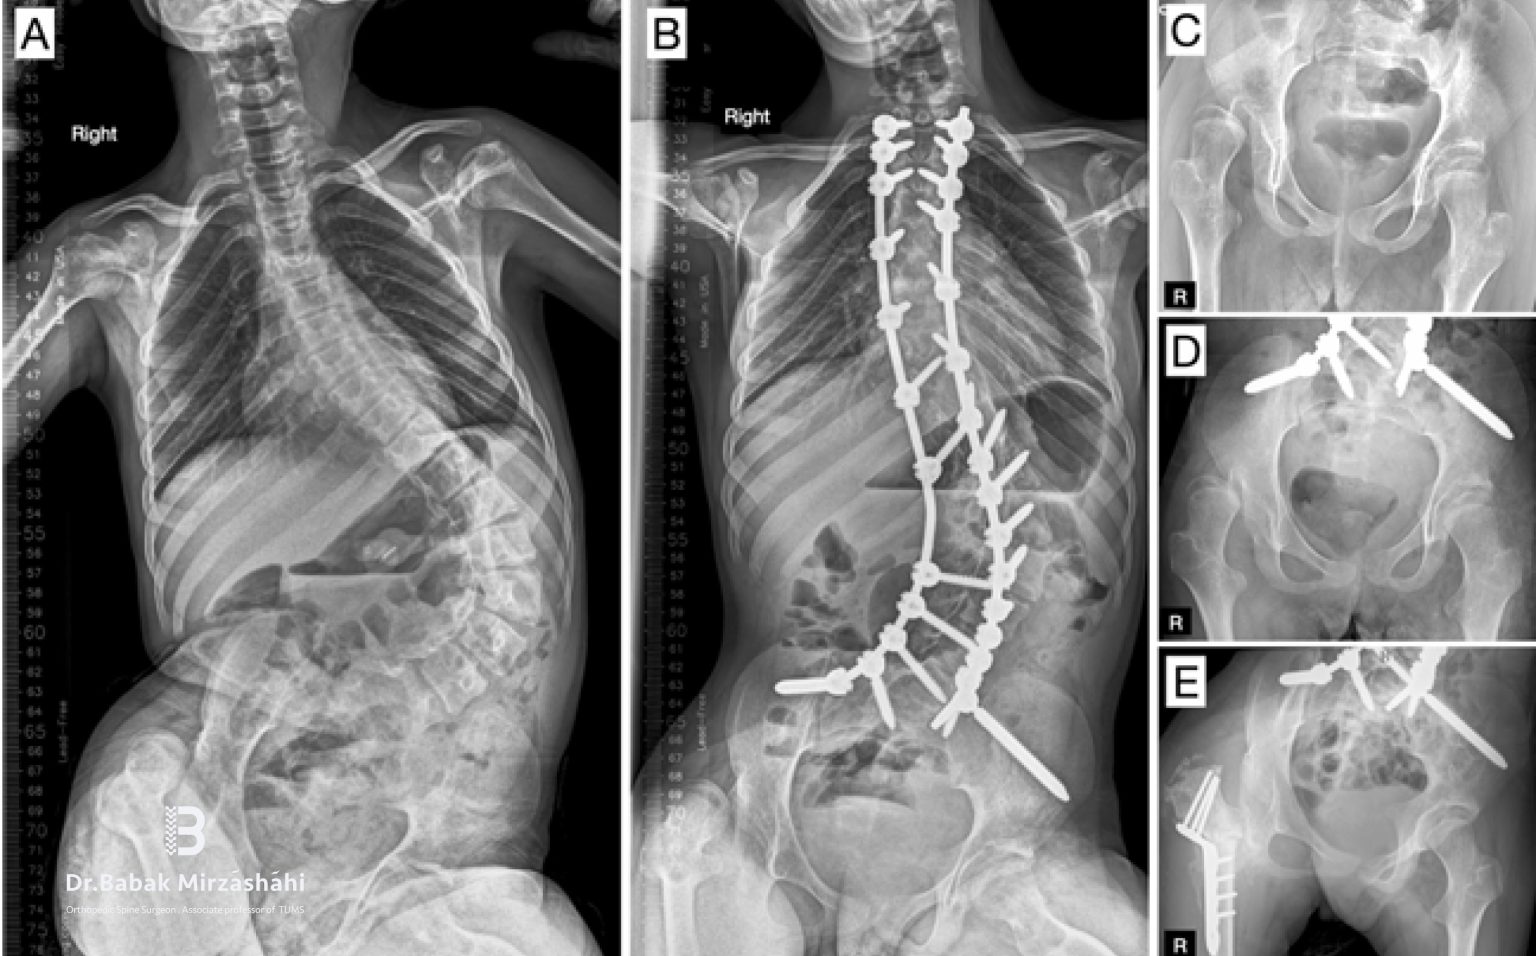

مدیریت درد، کنترل خونریزی و بهینهسازی تغذیه در جراحی اصلاح انحراف و ناهنجاری ستون فقرات مقدمه جراحیهای اصلاح انحراف ستون فقرات مانند اسکولیوز، کیفوز ... ادامه مطلب